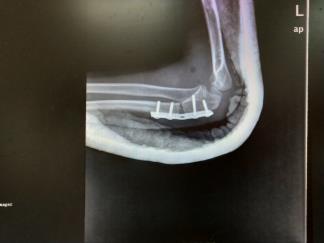

肱骨外髁陈旧性骨折